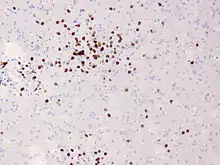

In Rasmussen's encephalitis, there is chronic inflammation of the brain, with infiltration of T lymphocytes into the brain tissue. In most cases, this affects only one cerebral hemisphere, either the left or the right. This inflammation causes permanent damage to the cells of the brain, leading to atrophy of the hemisphere; the epilepsy that this causes may itself contribute to the brain damage. The epilepsy might derive from a disturbed GABA release,[2] the main inhibitory neurotransmitter of the mammalian brain.